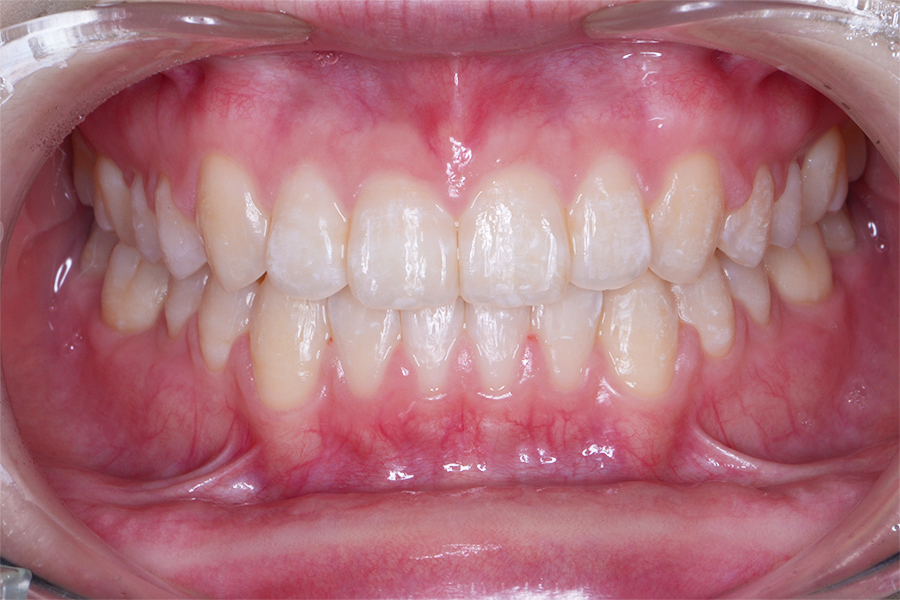

【20代女性】一本だけ引っ込んでいる。

ねじれも治したい

【矯正歯科治療】

- 担当医

- 三留先生

- 主訴

- 一本だけ引っ込んでいる。ねじれも治したい

- 期間

- 12か月

- 費用

- 治療費35万+35万(別途調整料)

- 治療内容

- 上下顎リンガル矯正(裏側矯正)

- 治療に伴うリスク

- 後戻り